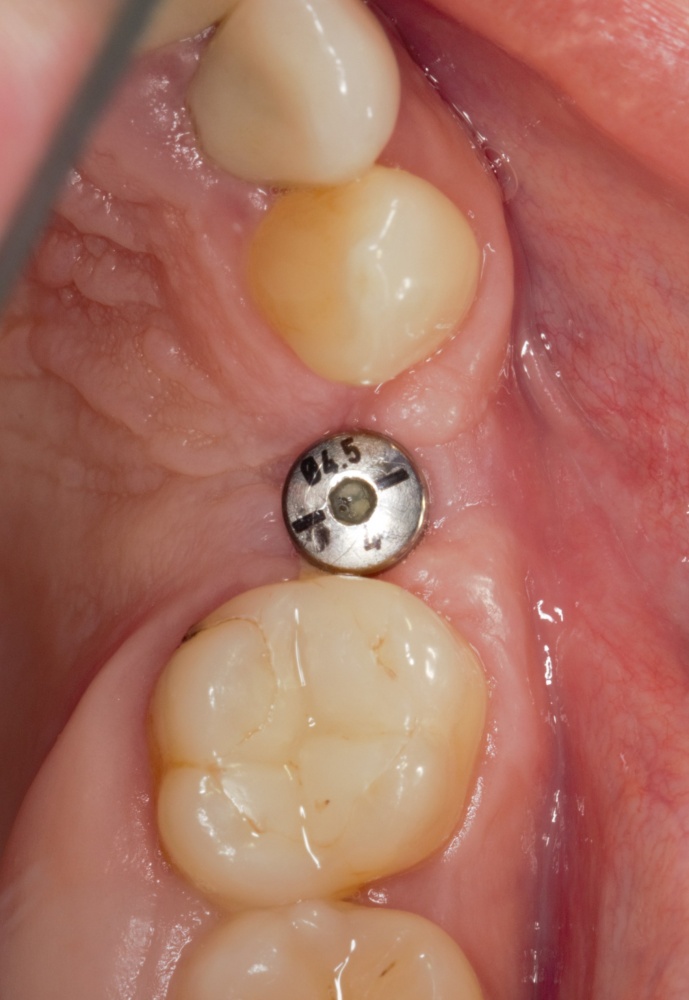

Теперь возьмём клинический случай (нижняя челюсть, отсутствия 35, 36, 37 зубов, атрофия альвеолярного гребня по ширине):

и рассмотрим его через парадигму методологического редукционизма. Или, если хотите, сквозь Бритву Оккама.

Мы имеем относительно небольшой дефект, не позволяющий, однако, установить имплантаты правильного размера в правильное положение. И два варианта остеопластической операции, НКР и АТККФ.